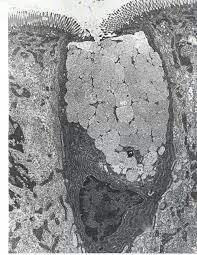

Parietal cell TEM "NOTICE apical occluding junction"

A : Lumen B : Microvilli C : Intracellular canaliculas D : Mitochondria